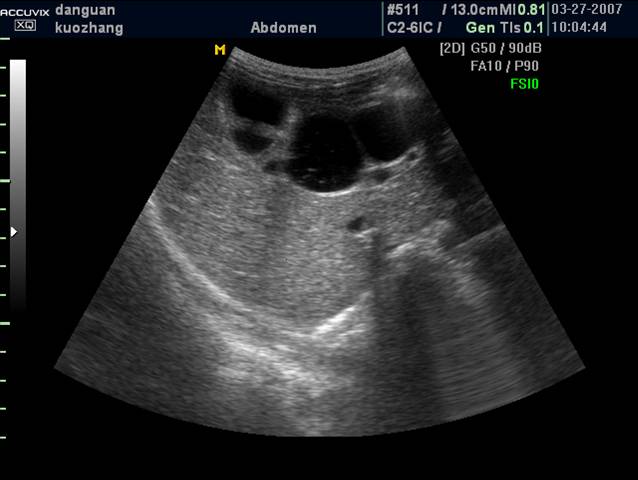

3 先天性胆管囊状扩张症